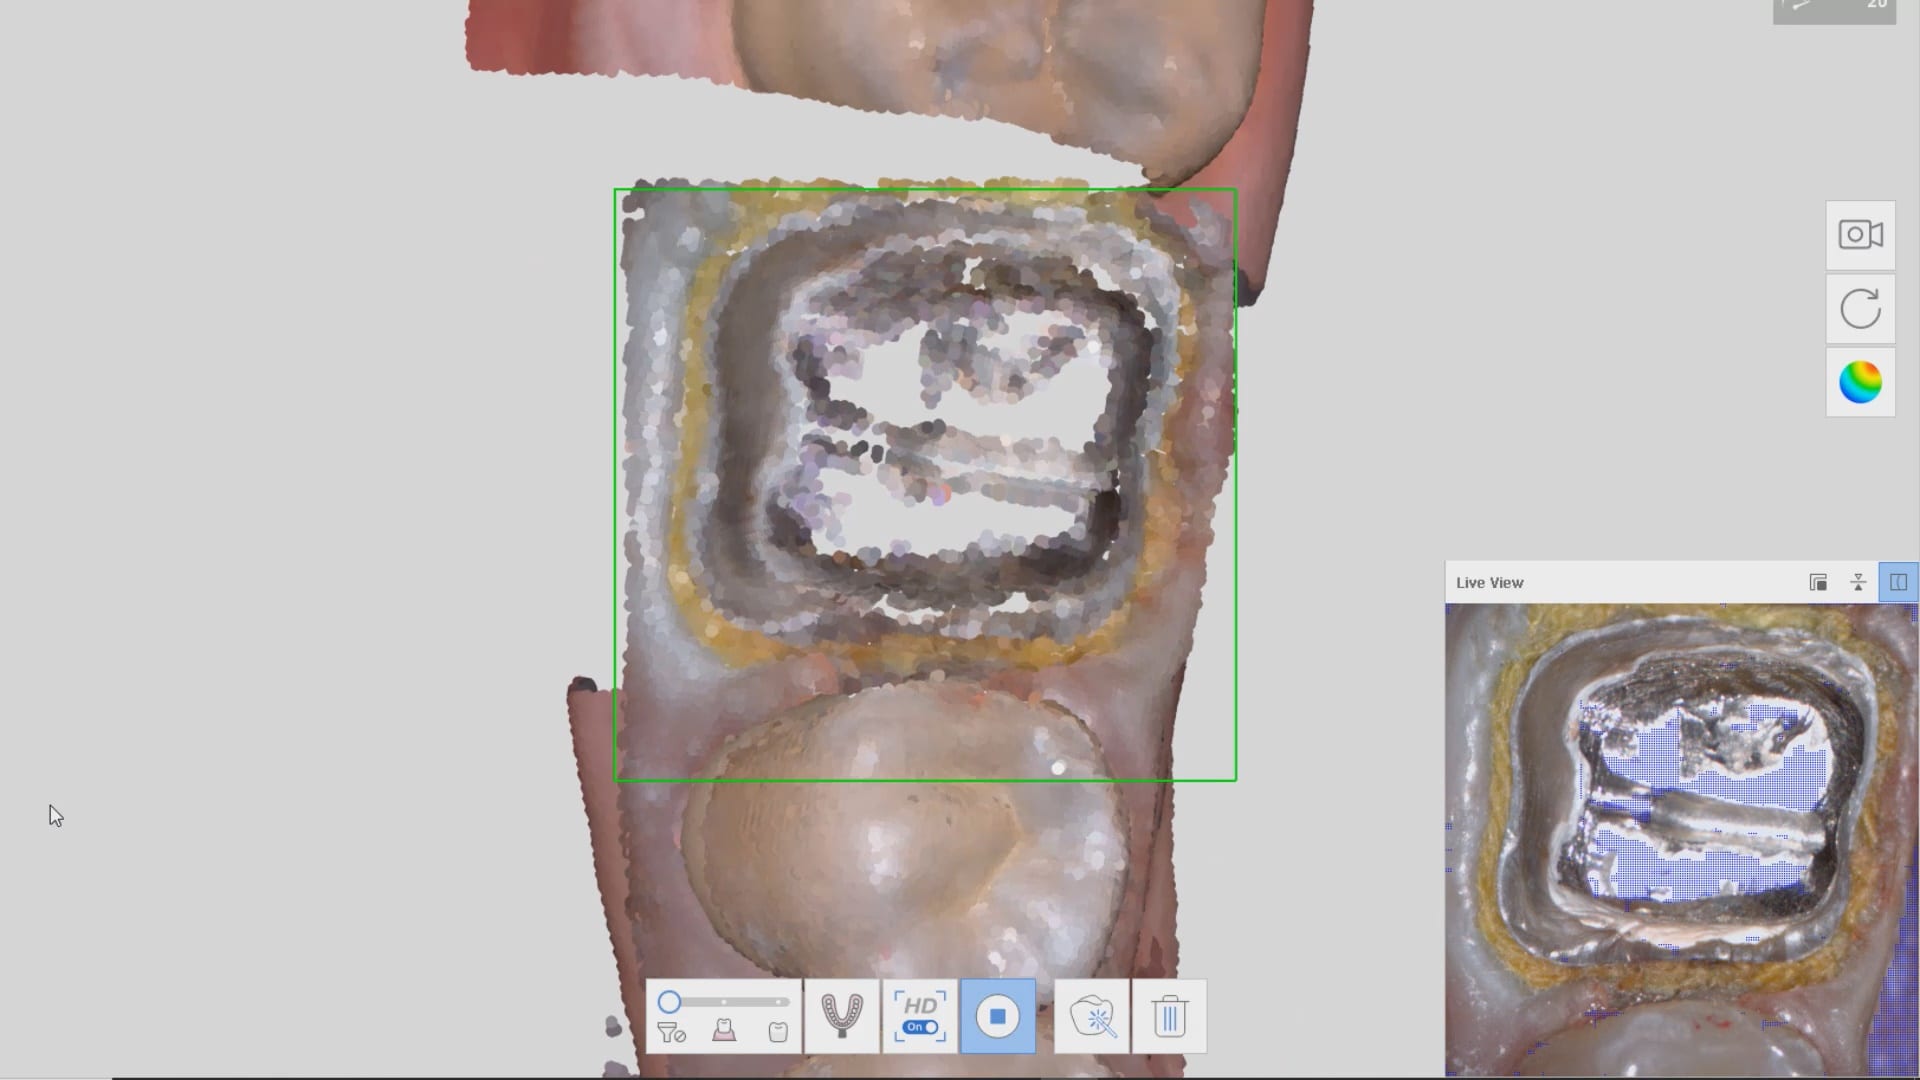

Full Arch Scan by The Shining 3D Aoralscan

March 16, 2020In this video we demonstrate how the Aoralscan can complete a full arch scan utilizing the basic principles of digital impressioning. Proper retraction, isolation, and scanning technique lead to high […]